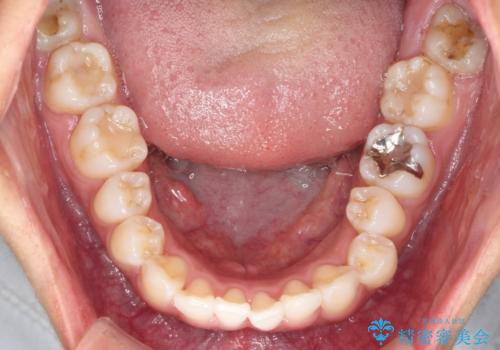

- 前歯のガタつき、突出感のある前歯の改善を求めて来院されました。

前歯の角度を改善し審美性を高めるとともに、奥歯のガタつきも並べ直すことで安定した咬合関係の確立を目指します。

歯列の側方拡大をしっかりと行ったことで歯を抜かずに前歯の角度をしっかりと改善することができました。